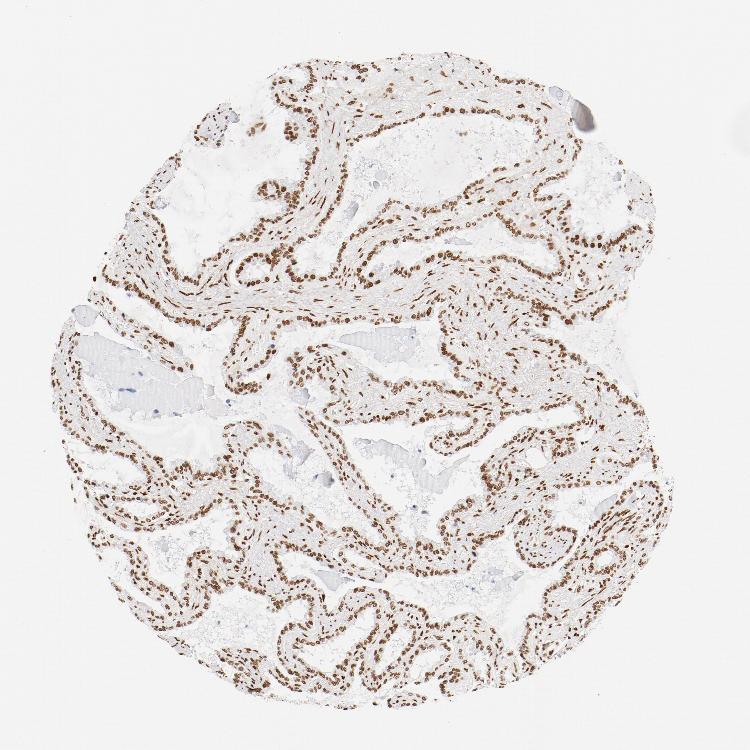

SEMINAL VESICLE - Antibody stainingi

Antibody staining in the annotated cell types in the current human tissue is reported as not detected, low, medium, or high, based on conventional immunohistochemistry profiling in selected tissues. This score is based on the combination of the staining intensity and fraction of stained cells.

Each image is clickable and will lead to virtual microscopy that enables deeper exploration of all samples and also displays staining intensity scores, fraction scores and subcellular localization as well as patient and tissue information for each sample.

Antibody HPA018987Antibody HPA044971Antibody CAB004217

Glandular cells Not detectedMediumHigh